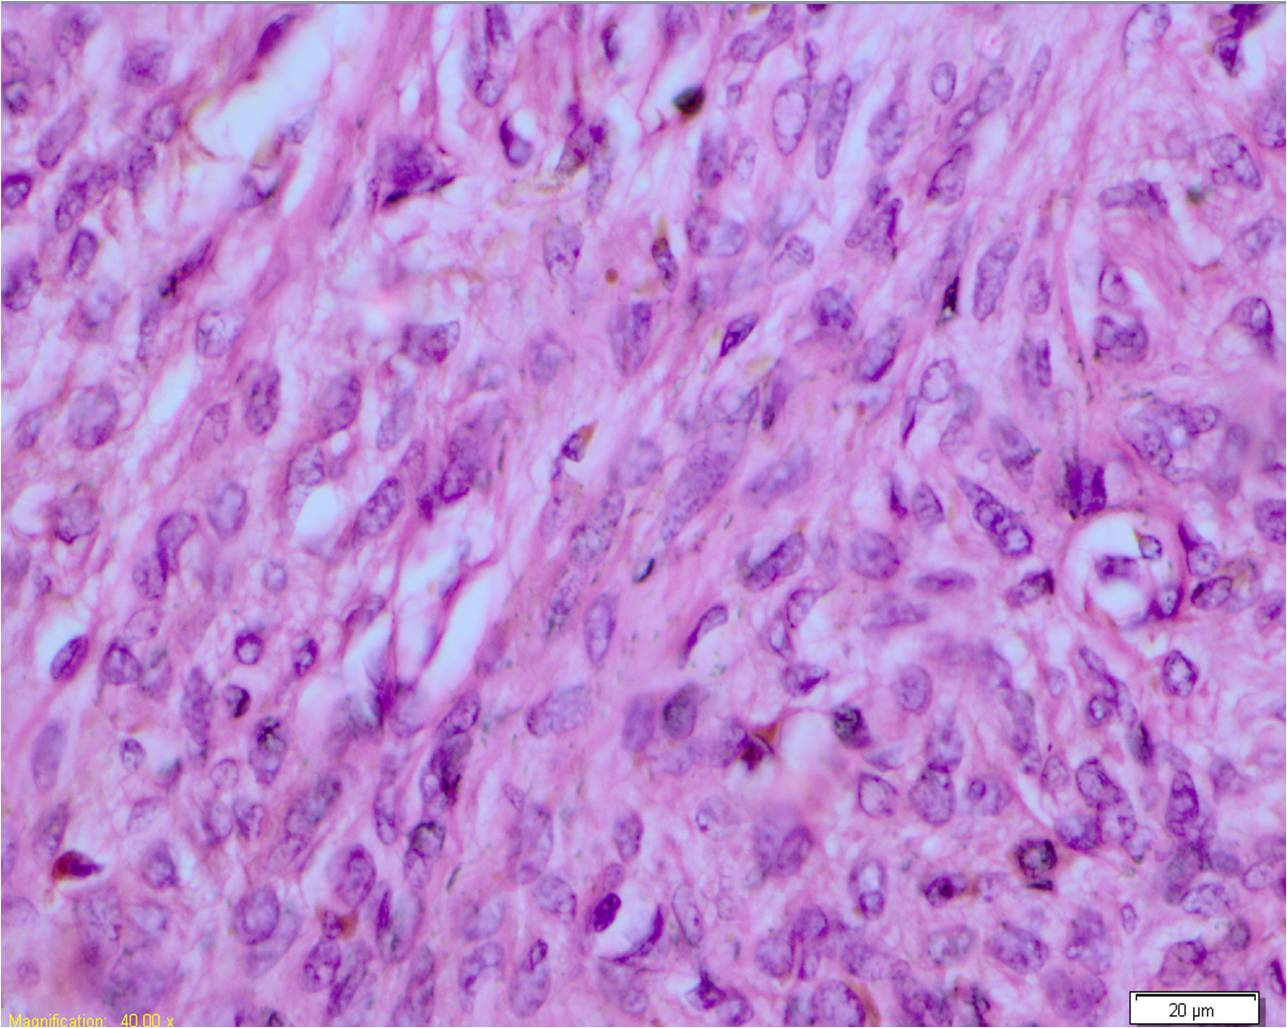

Микропрепараты: Лимфогранулематоз и Нодулярный Склероз